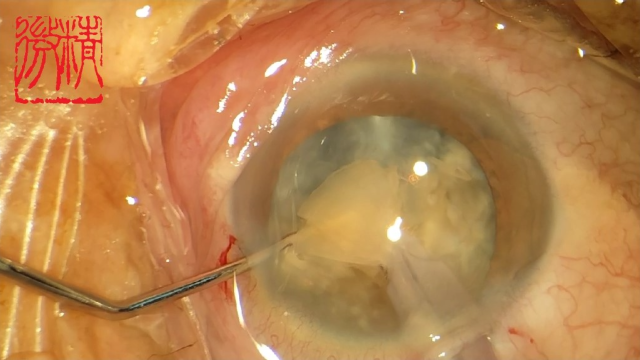

大瓜:湖南省人民医院副院长出轨眼科主任?

号外号外,湖南省人民医院副院长祖雄兵和眼科主任医师曾琦被指存在不正当关系,并有不雅视频传出。对此,医院工作人员回应:组织正在调查,请给医院宣传部门联系。当地卫生健康委员会对此回应:暂未接到相关的信访反映。祖雄兵为湖南省人民医院副院长,泌尿外科学科带头人。曾琦,博士,主任医师,硕士研究生导师。现任湖南省人民医院眼科副主任、眼科一病区主任,湖南省卫生健康高层次青年骨干人才,湖南省预防医学会眼病防治专业委员会主任委员、湖南省女医师协会眼科专业委员会主任委员、湖南省医学会眼科学专业委员会防盲学组副组长、湖南省医学会眼科学专业委员会眼外伤及职业病学组副组长、湖南省医学会眼科学专业委员会白内障学组副组长、